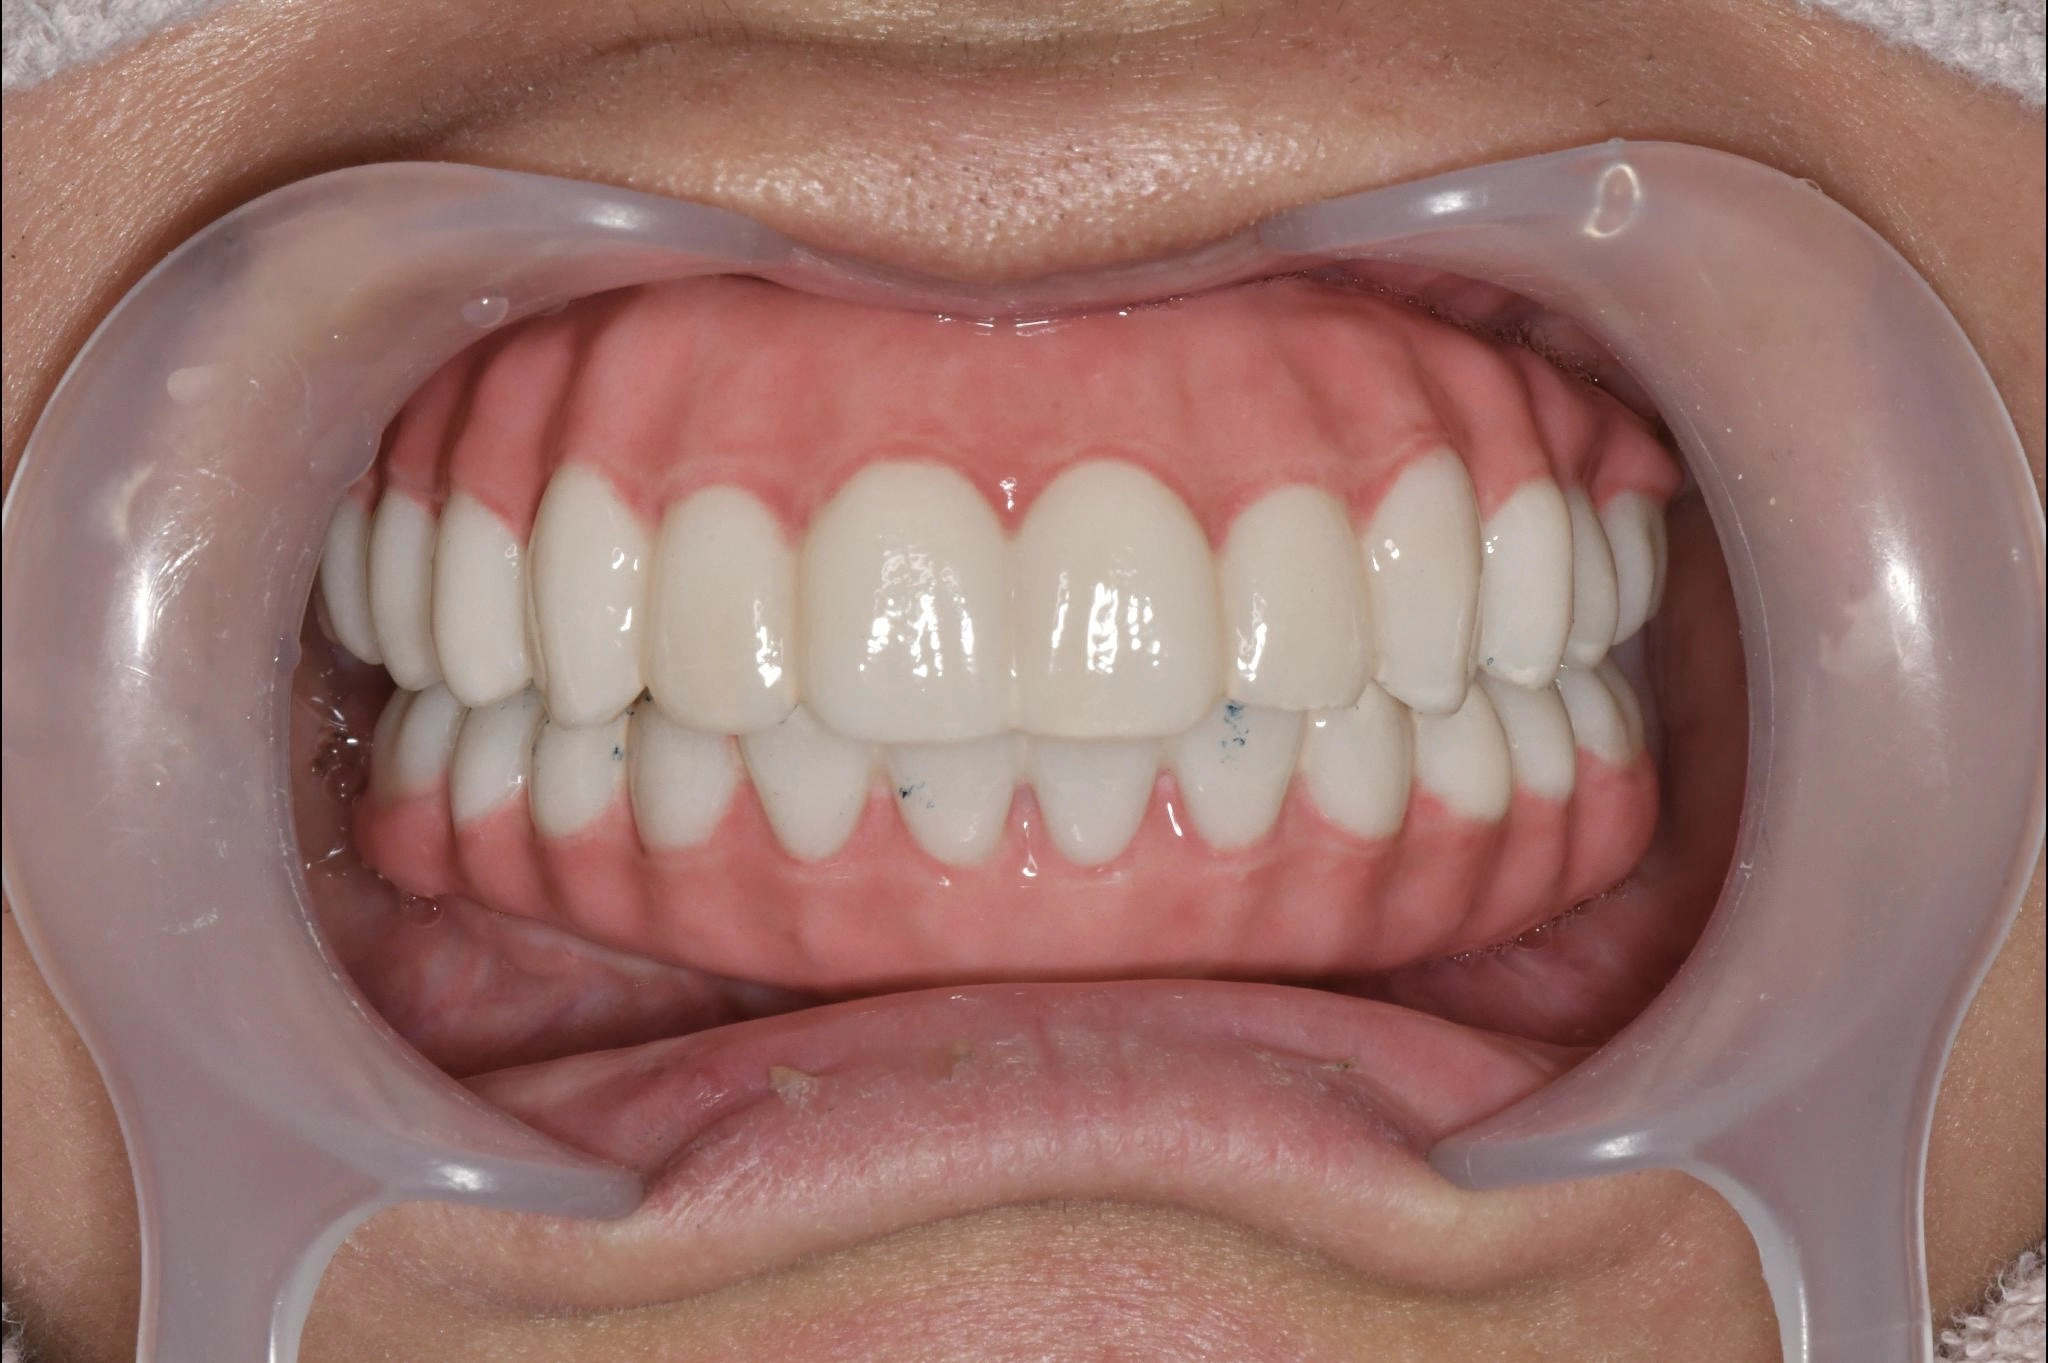

術後